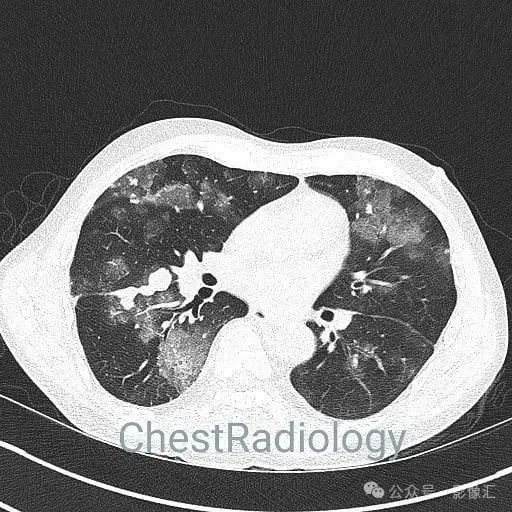

咯血患者,肺部弥漫磨玻璃,细节决定成败?

成年男性,咯血,细节决定成败,你看到了吗?欢迎评论区留言